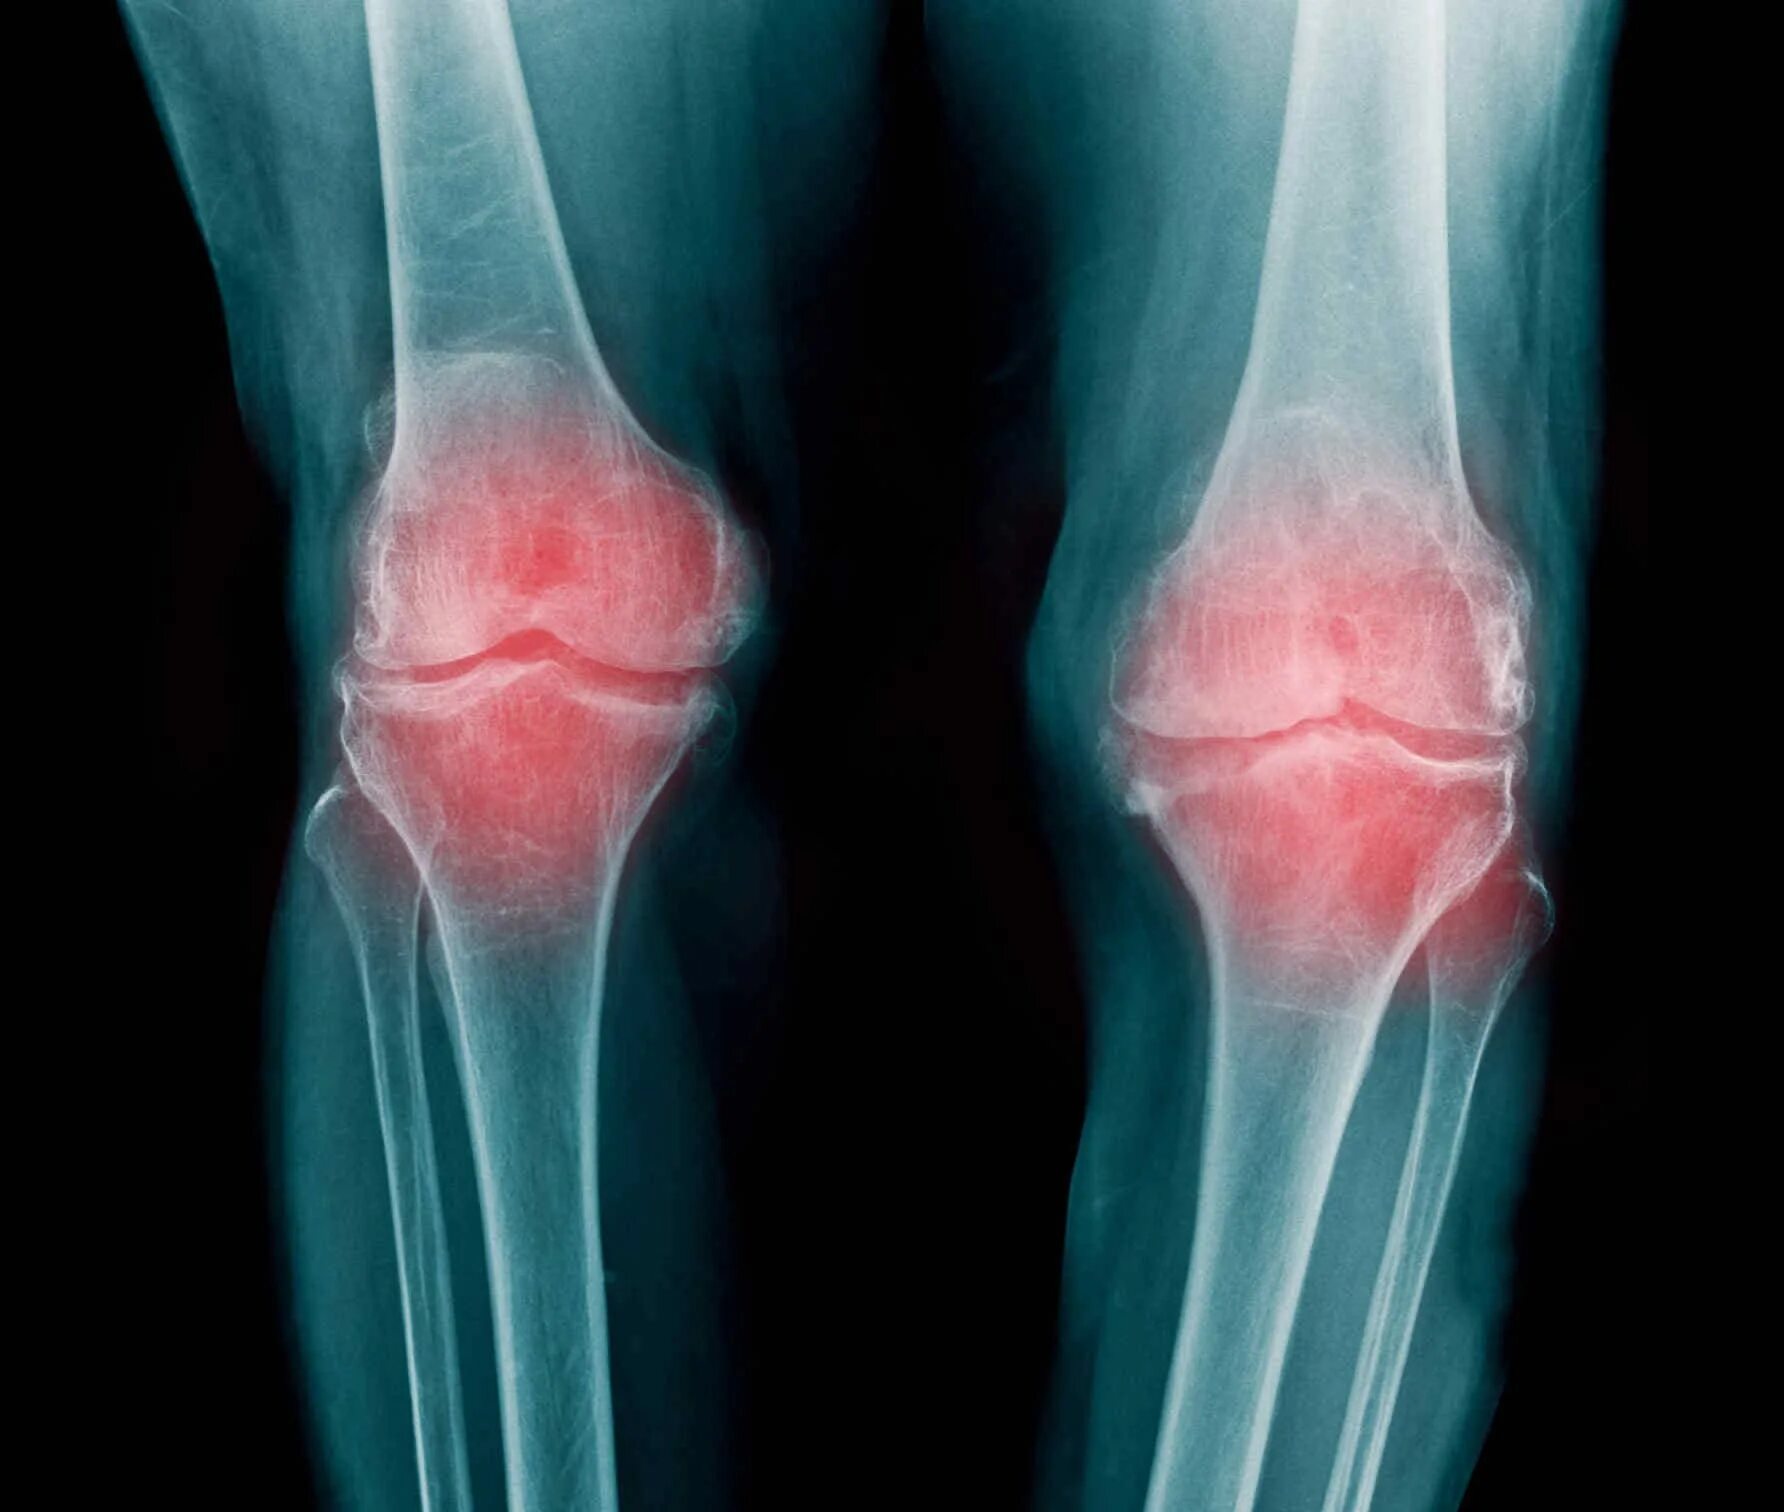

Ревматизм ног